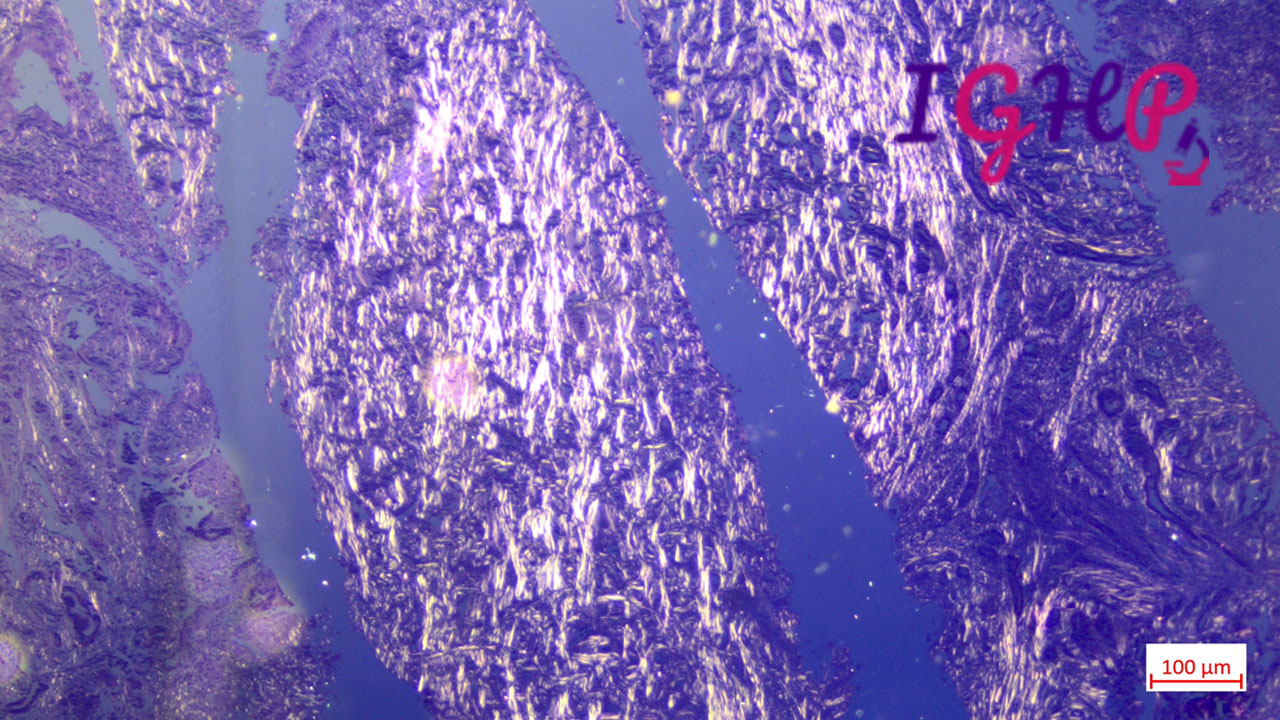

Special Stains Performed-

MT stain performed showed dense sclerotic desmoplastic stroma